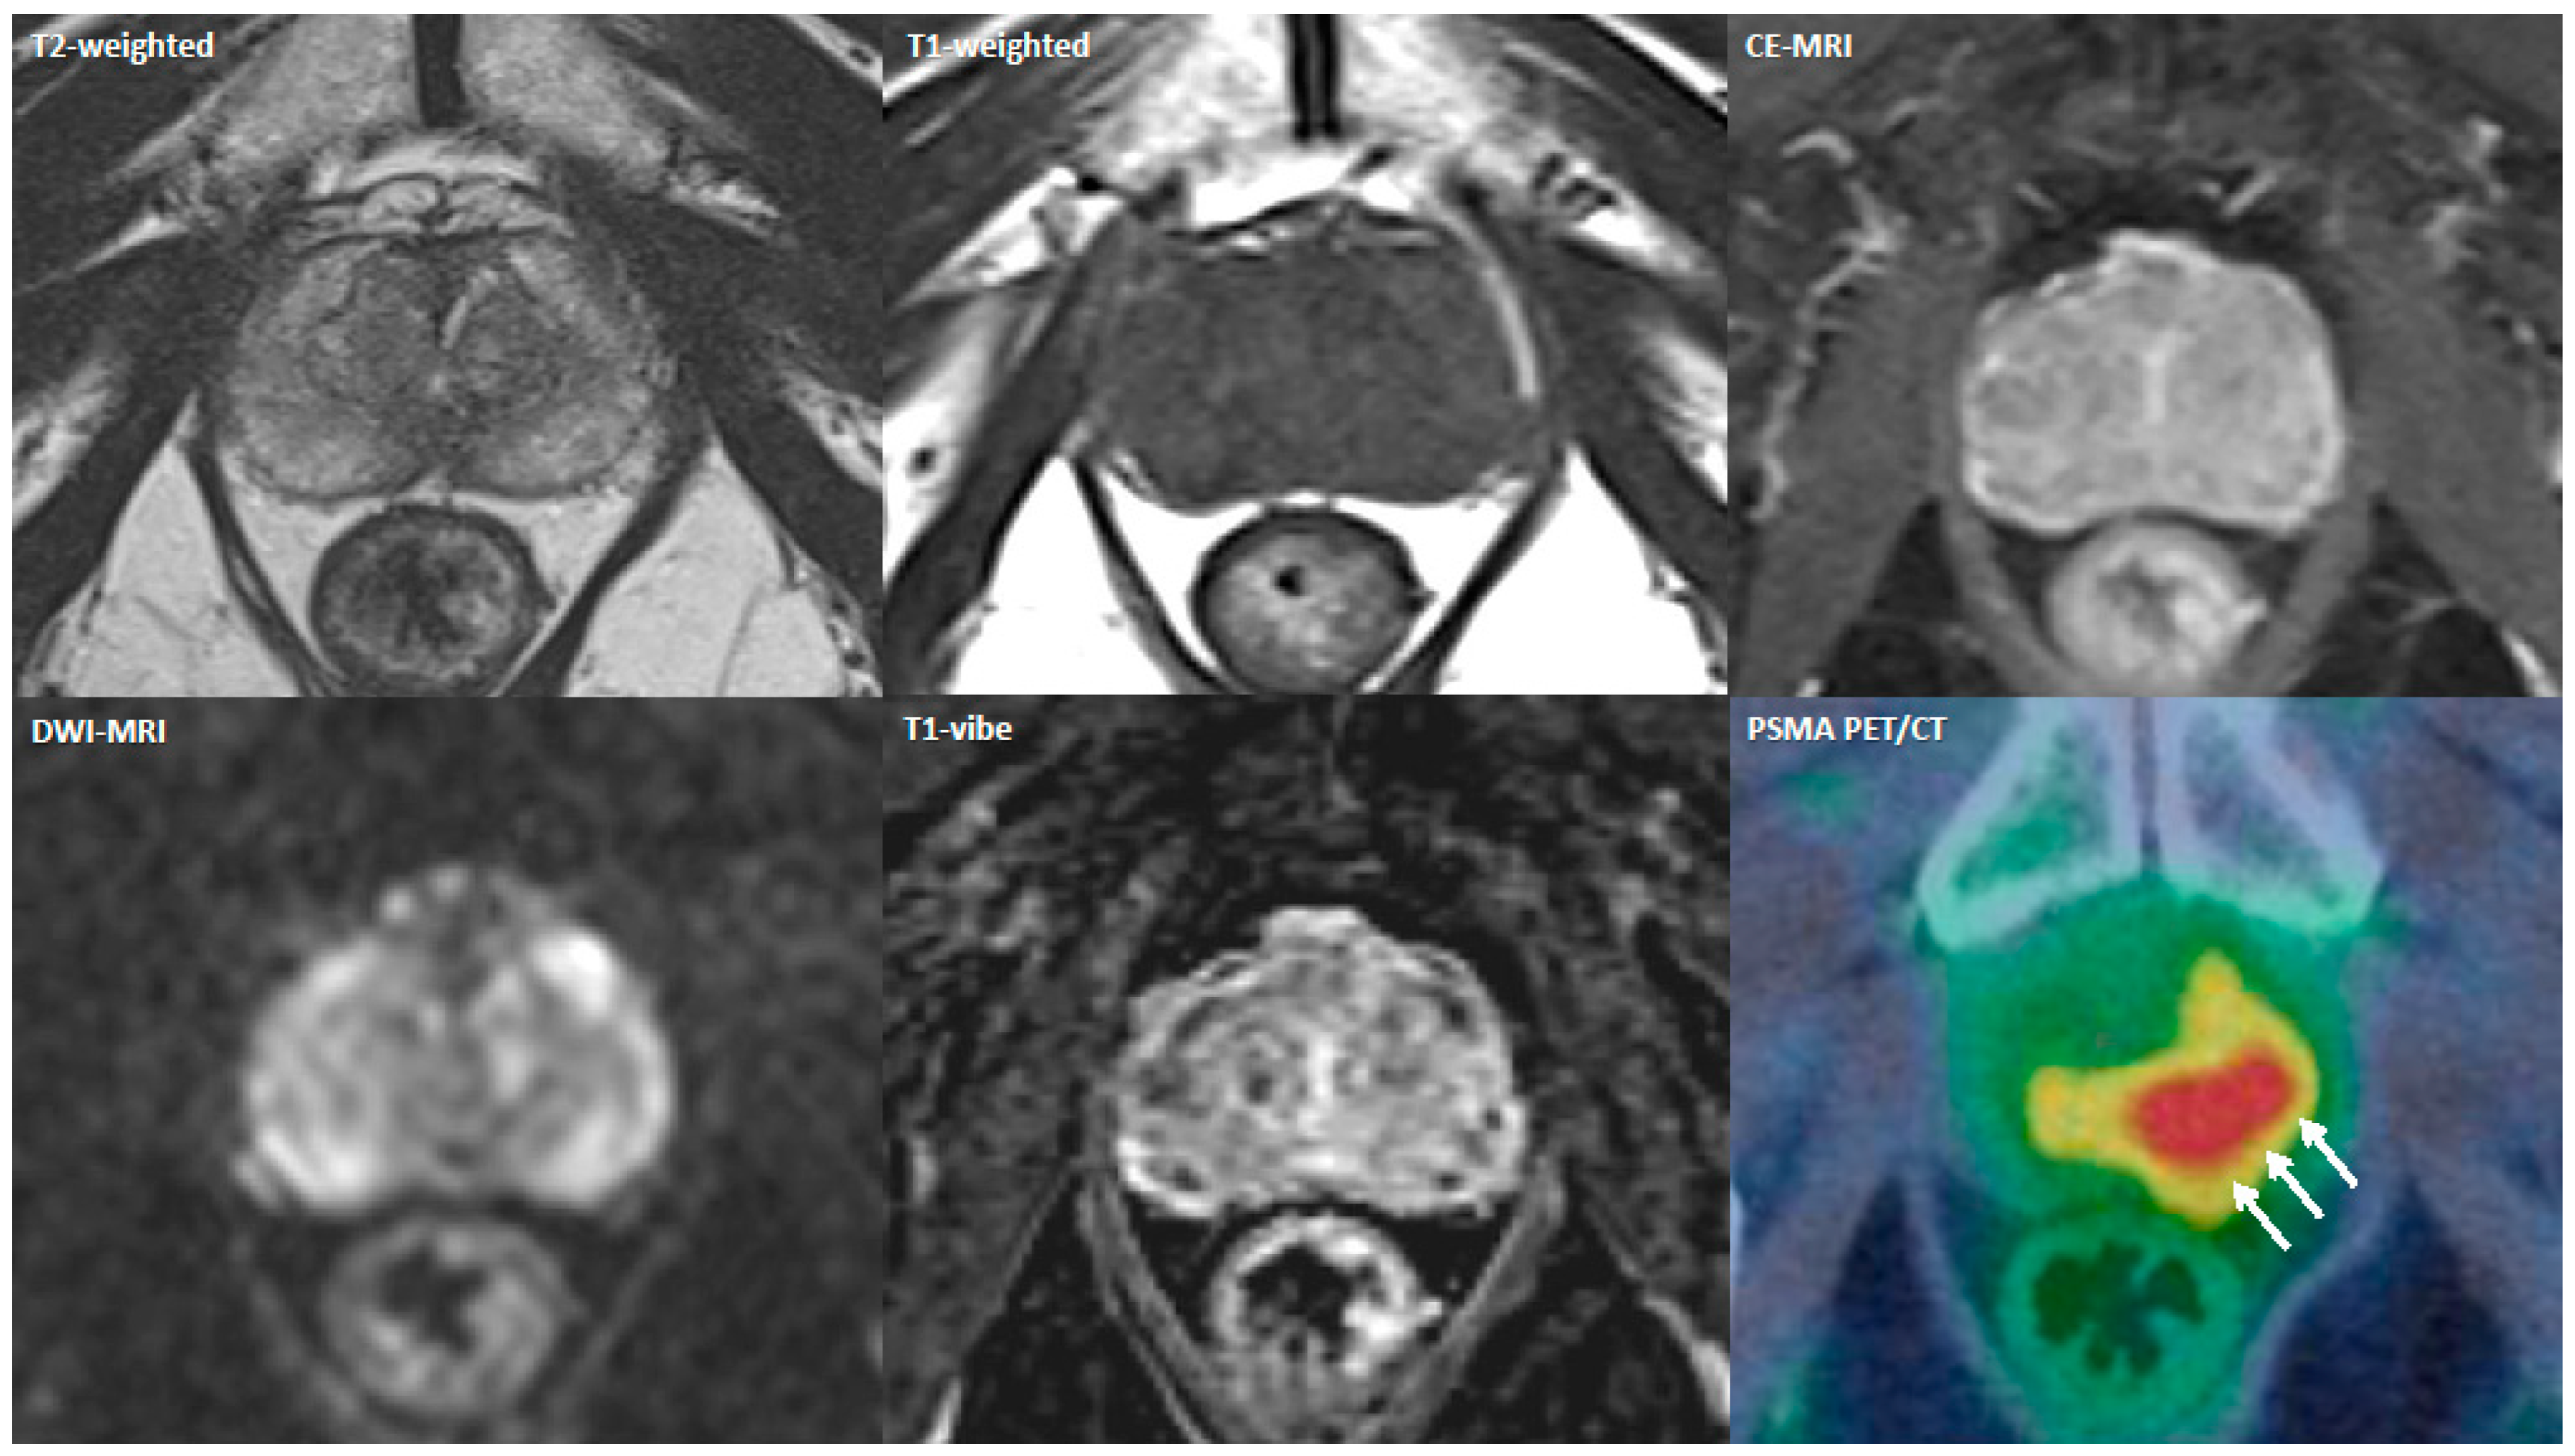

- Lopci, E.; Lughezzani, G.; Castello, A.; Saita, A.; Colombo, P.; Hurle, R.; Peschechera, R.; Benetti, A.; Zandegiacomo, S.; Pasini, L.; et al. Prospective Evaluation of 68Ga-labeled Prostate-specific Membrane Antigen Ligand Positron Emission Tomography/Computed Tomography in Primary Prostate Cancer Diagnosis. Eur. Urol. Focus 2021, 7, 764–771. [Google Scholar] [CrossRef]